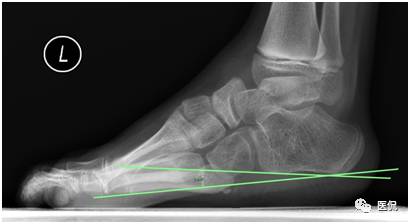

在提供的X线负重侧位图像上,关于角度的测量,下列正确的是(多选)

A 跟骨倾斜角的测量:跟骨下缘的连线、跟骨后结节低点与第五跖骨远端低点的连线,二者的夹角

B 跟骨中轴线的测量:与跟骨倾斜角的测量一致

C 距骨中轴线的测量:距骨距舟关节的中点与过滑车横断面的中点的连线

D 距骨中轴线的测量:距骨头低点与过滑车横断面低点的连线

E 第一跖骨中轴线的测量:第一跖骨近端与远端中点的连线

答案解读:A B E

解析:根据国外最新标准,在原有标准基础上略有修改,更能准确客观的进行数据的测量,测量如下(以左足为例):如下图。